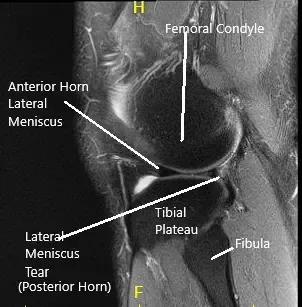

MRI of the left knee suggested a lateral meniscal tear.. There was mild partial-thickness cartilage loss along the central trochlear groove and in the lateral compartment.

MRI of the Knee in coronal and sagittal sections